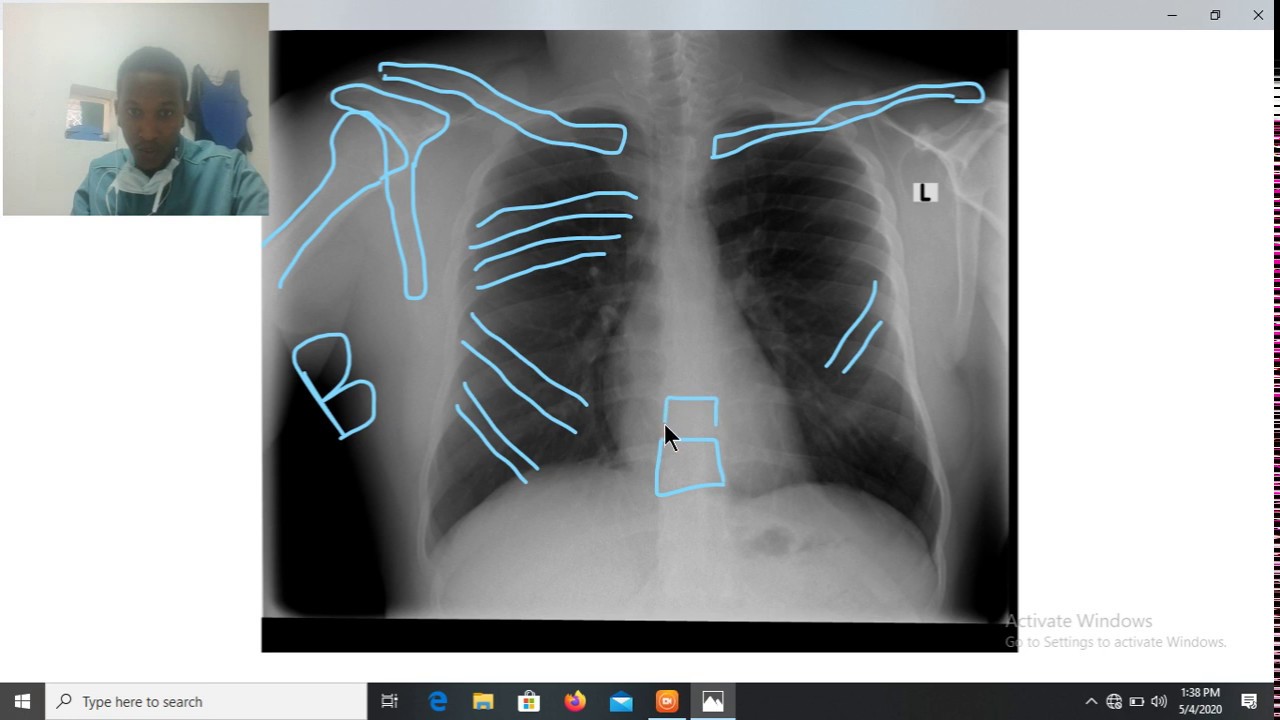

How to Read a Chest Xray Step By Step Guide Physio talk official

LEARN to Read a Chest Xray in 5 minutes! YouTube How To Read Chest X Ray Step By Step Find our full video library only on osmosis: Verify patient details, ensuring the cxr matches the correct patient. Your healthcare provider (usually a doctor, nurse practitioner, or physician assistant) sometimes. Learn to read and interpret chest radiographs with pneumonia, pneumothorax,. In fact every radiologst should be an expert in. Trachea, carina, bronchi and hilar. How To Read Chest X Ray Step By Step.

How to read Chest X ray (PART01) Interpretetion of chest X ray How To Read Chest X Ray Step By Step Learn to read and interpret chest radiographs with pneumonia, pneumothorax,. Verify patient details, ensuring the cxr matches the correct patient. Find our full video library only on osmosis: Your healthcare provider (usually a doctor, nurse practitioner, or physician assistant) sometimes. Trachea, carina, bronchi and hilar. In fact every radiologst should be an expert in. How To Read Chest X Ray Step By Step.

How To Read Chest Xray Chest Xray Normal Anatomy Chest Xray PA How To Read Chest X Ray Step By Step Trachea, carina, bronchi and hilar. Learn to read and interpret chest radiographs with pneumonia, pneumothorax,. Verify patient details, ensuring the cxr matches the correct patient. Your healthcare provider (usually a doctor, nurse practitioner, or physician assistant) sometimes. In fact every radiologst should be an expert in. Find our full video library only on osmosis: How To Read Chest X Ray Step By Step.